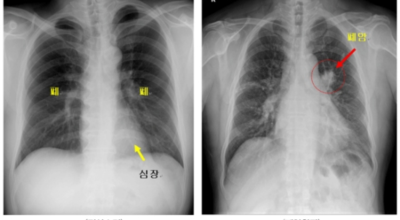

폐암 검사는 X-ray를 통해서 검사하는데 , 크기가 작거나 구석에 위치한 경우 확인이 어려운 경우도 있습니다. 그리고 조직 검사를 통해서 정확한 진단을 하게 돼요. 폐암이 발견되면 종양의 크기나 전이 여부 , 위치에 따라서 수술 여부를 결정하게 돼요.